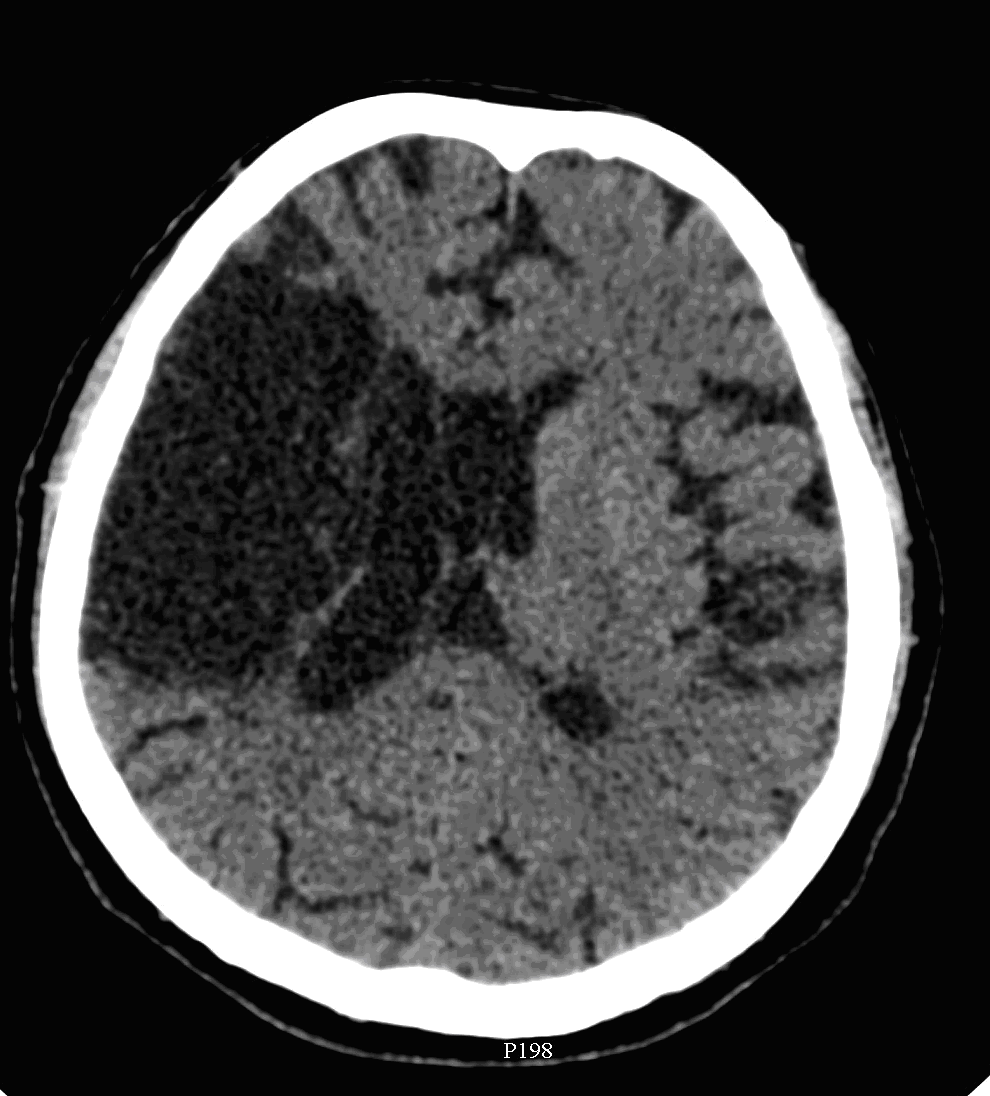

On CT images acute bleeding always presents as hyperdensity. (One has to keep it mind that hyperdensity of the blood is affected by the hematocrit levels, hence making the diagnosis more difficult.) Intraparenchymal blood is dominated by a destructive appearance (mass-effect) and it is surrounded by hypodensity as a sign of perifocal edema. It often breaks into the ventricles. In patients lying in a supine position they collect (sediment) at the occipital horn of the lateral ventricles, creating a hyperdense liquid-to-liquid levels. Later on, the density of blood decreases and shows a peripheral ring or rim-like contrast enhancement without mass-effect.

Although, subarachnoid hemorrhage (SAH) is most often caused by the rupture of a berry aneurysm, arteriovenous malformation (AVM) and trauma can also lead to it. SAH is typically located at the basal subarachnoid spaces, which then propagates along the lateral fissures or it fills up the interhemispheric fissure till the convexities. The main collection of the blood is usually indicative of the source of origin. In cases of parenchymal spread the mechanism, whether it broke in, or it broke out from the parenchyma could represent a differential diagnostic challenge. When accompanied by brain edema, the consequent herniation can result in parenchymal infarcts as well.